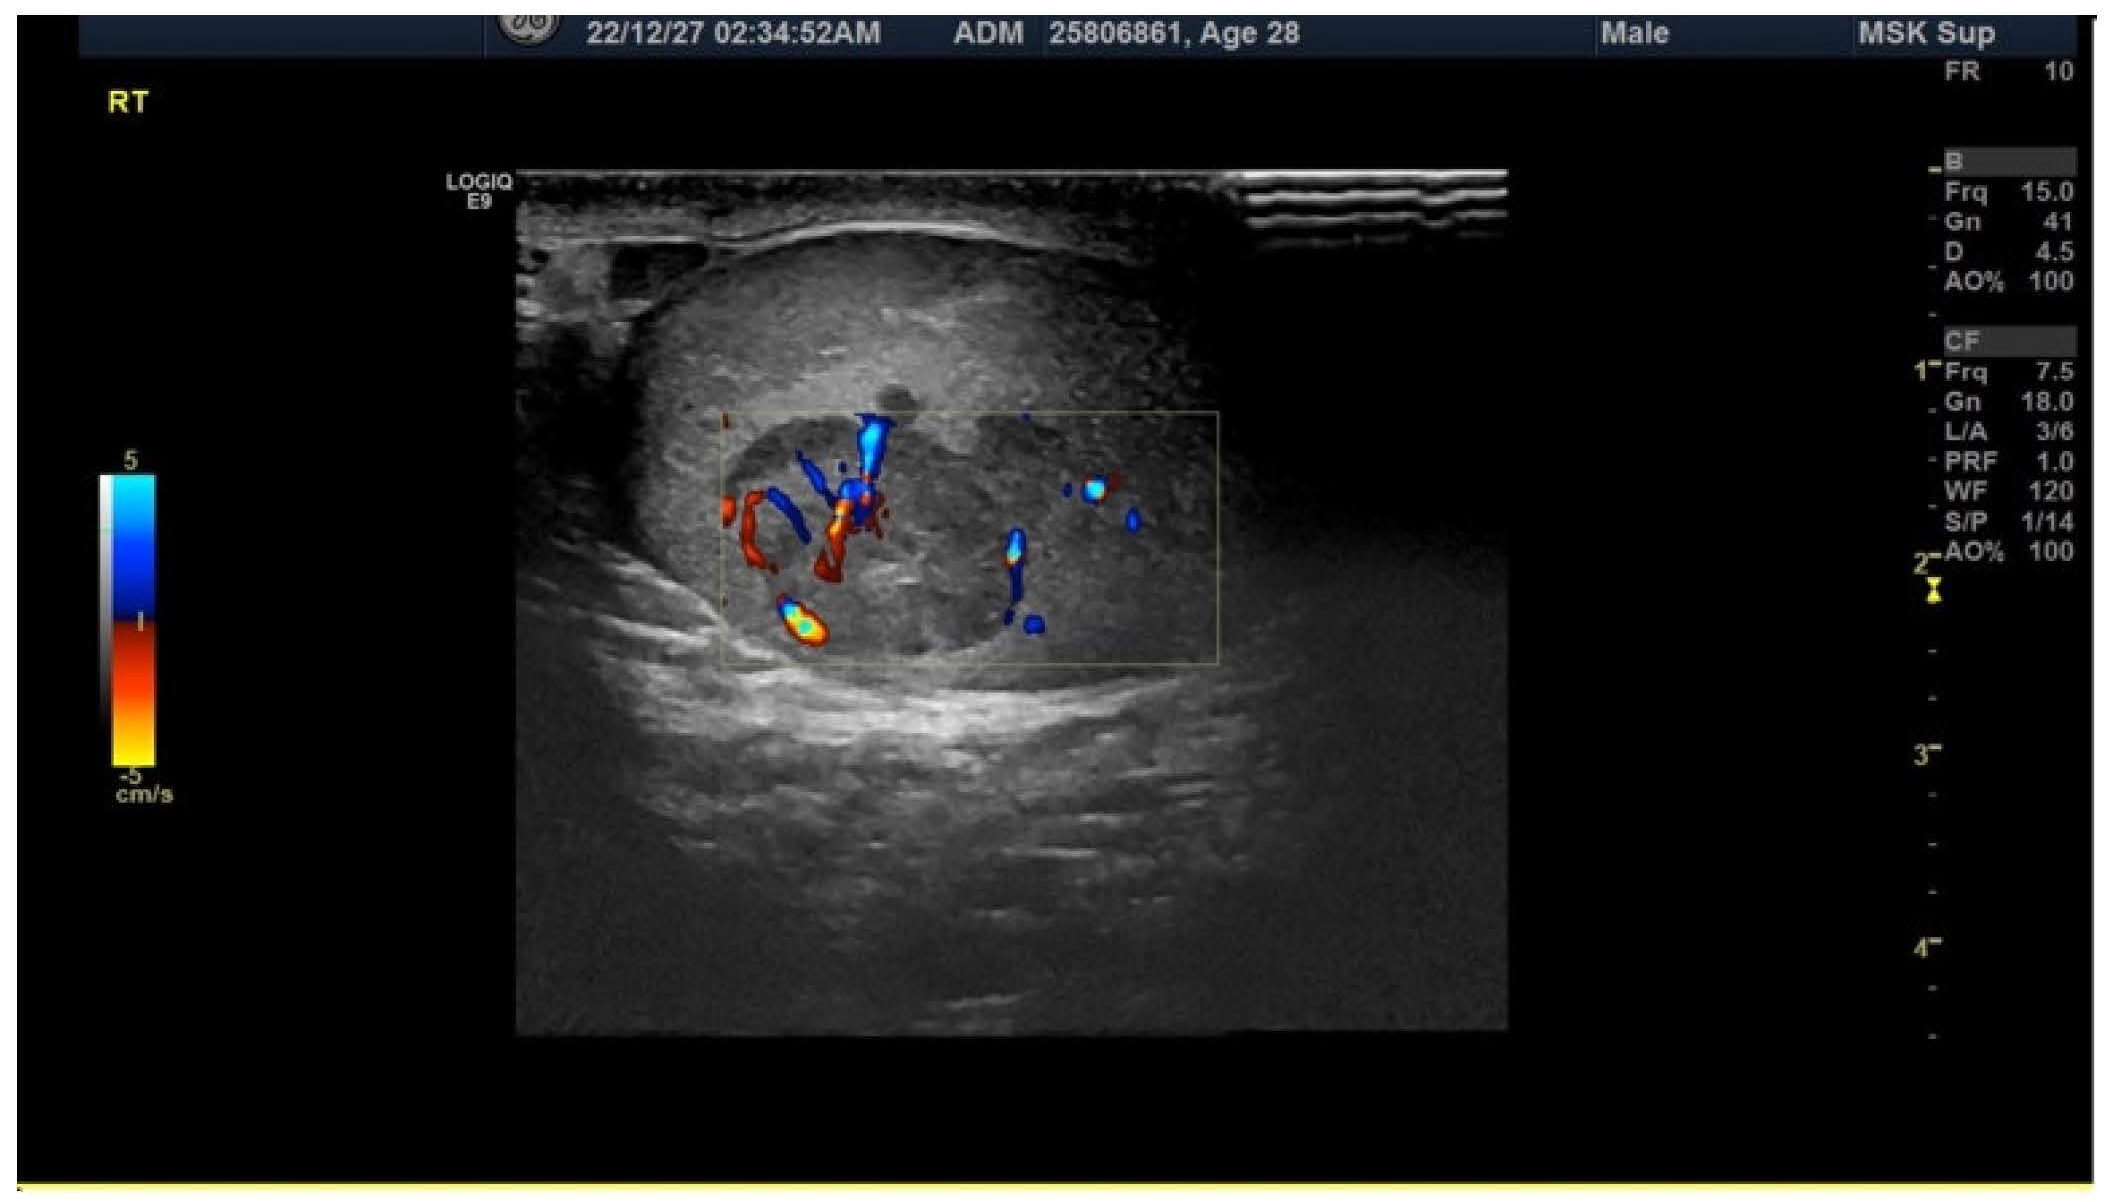

2. Case Presentation